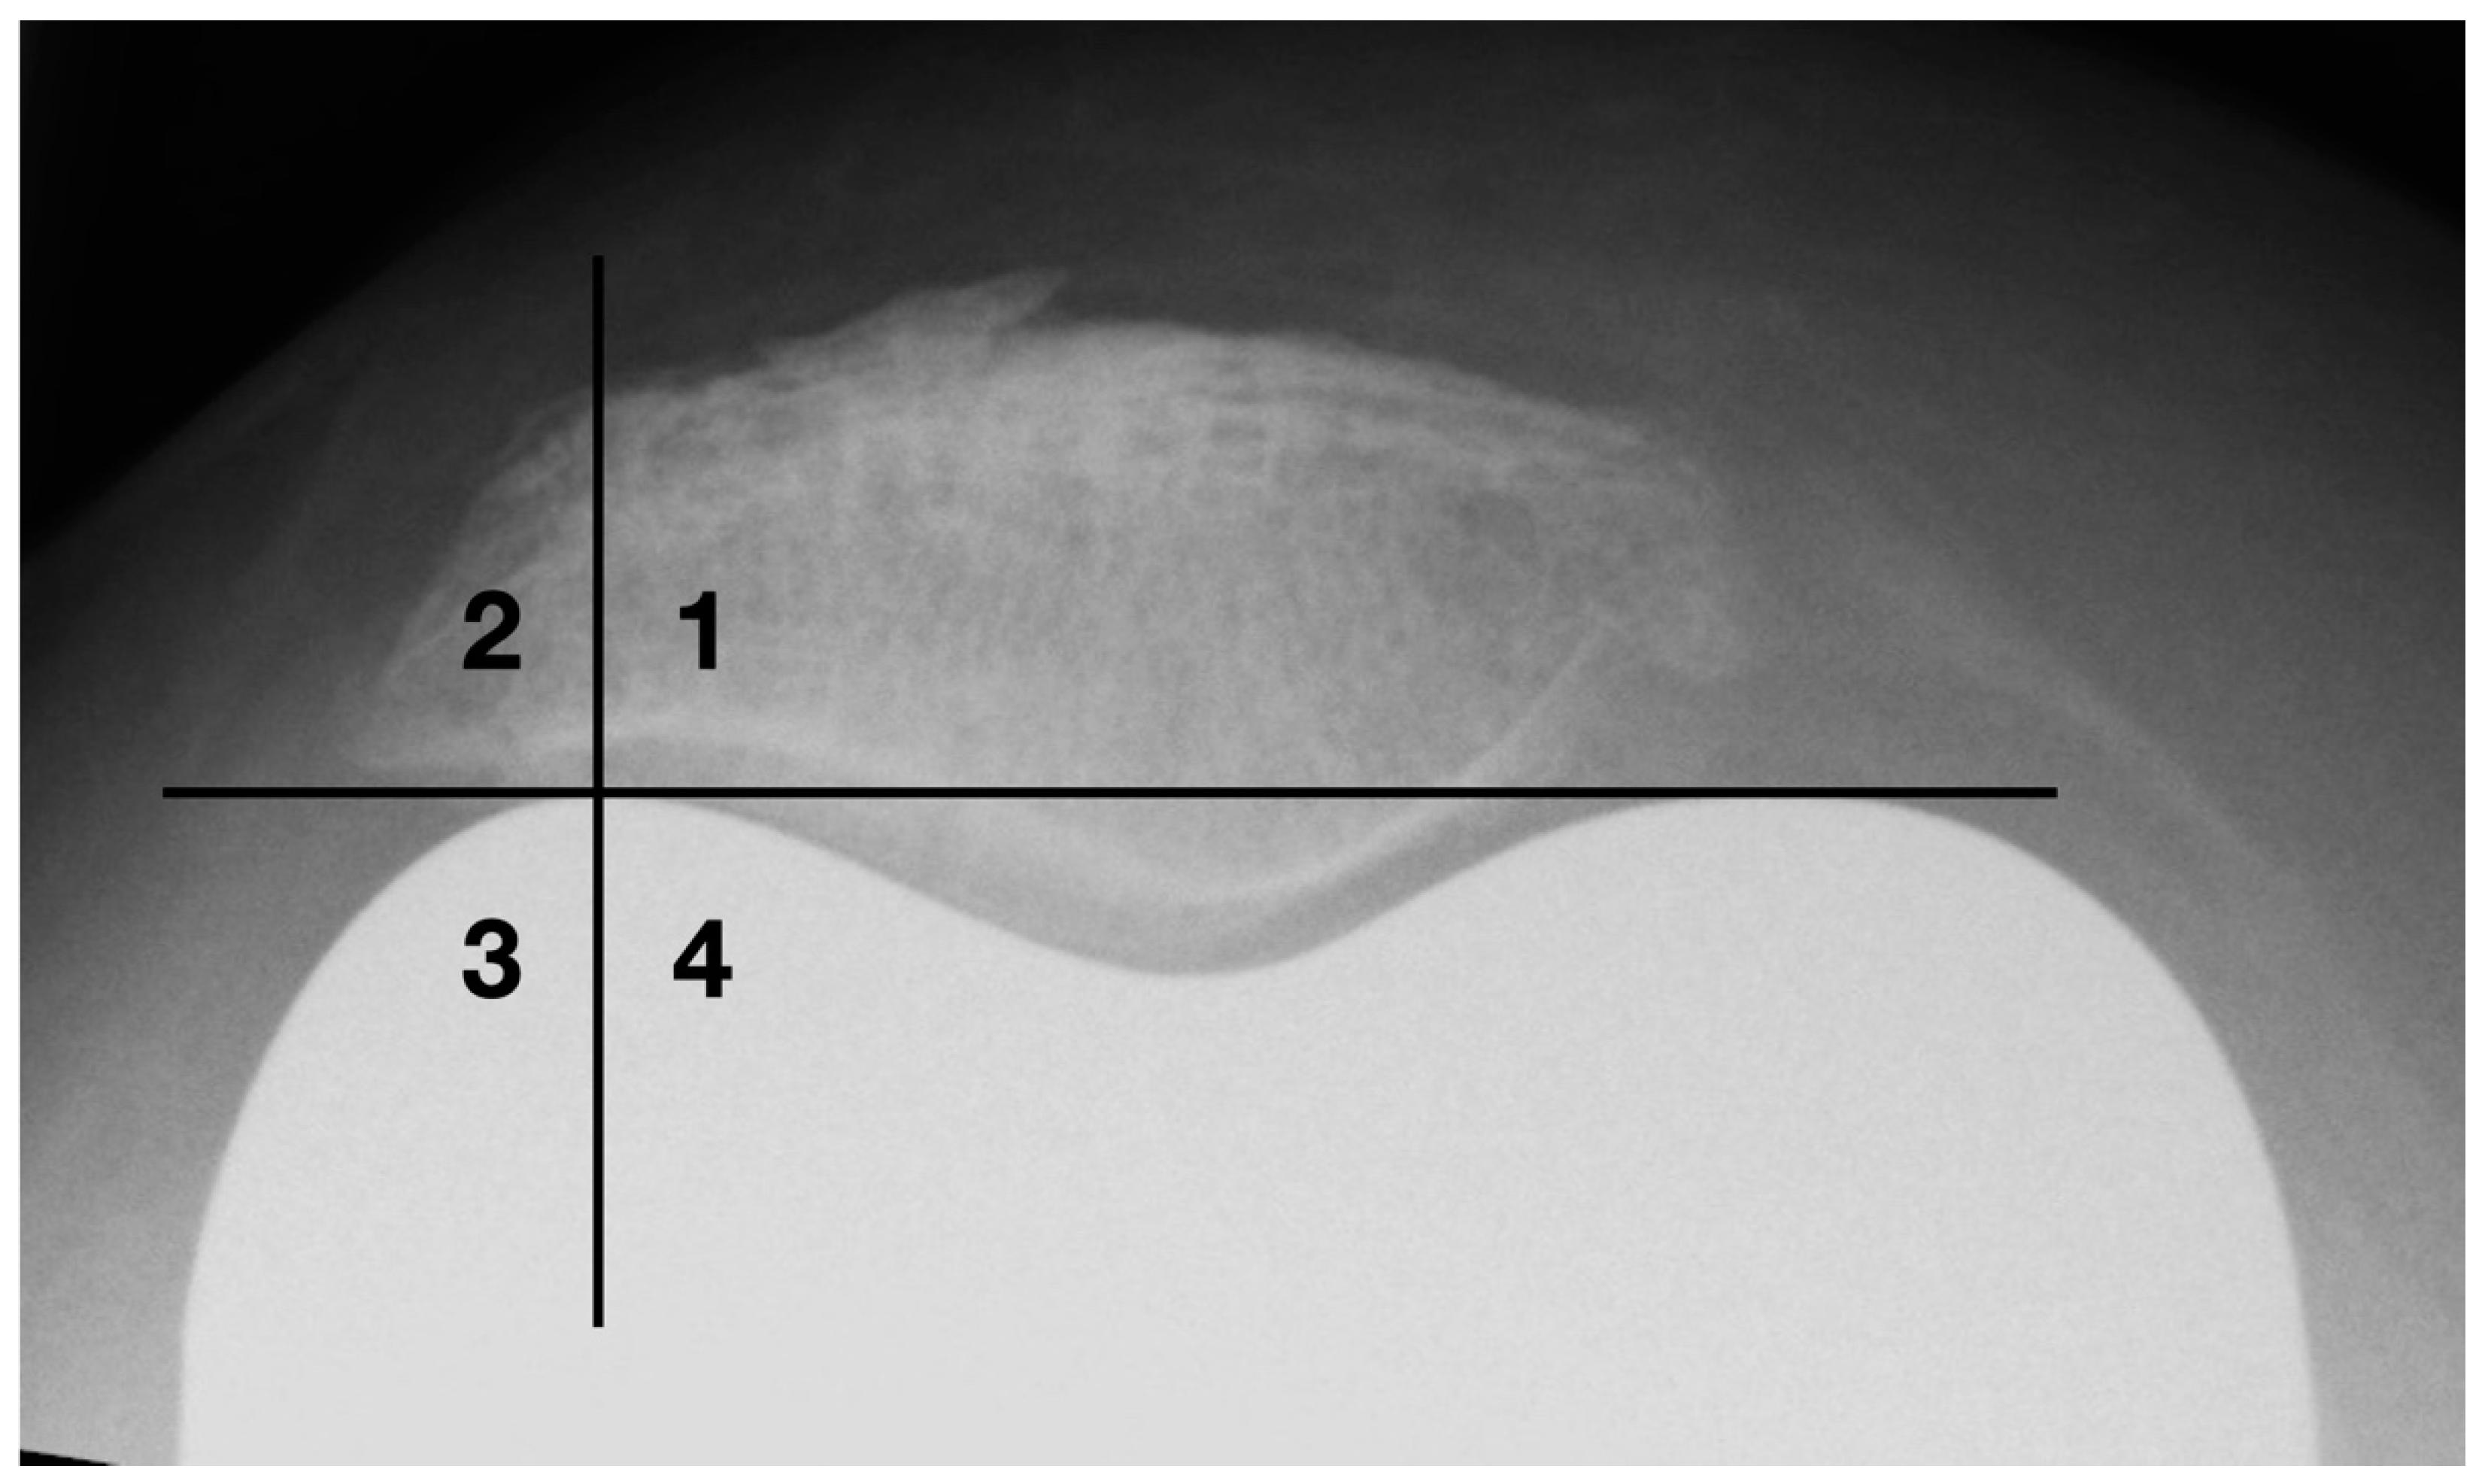

Osteophytes are one of the basic radiographic signs in osteoarthritis diagnostics [27]. During surgical joint replacement, osteophytes are usually removed. Left lateral osteophytes may lock and lead to compulsory guiding of the patella. This results in patellofemoral constraint, which is a common cause of functional limitations and postoperative pain in the femoropatellar joint [11]. A quadrant model was used to classify the lateral bony attachments (see Figure 7). The horizontal division is made at the level of the apices of the femoral condyles. The vertical dividing line runs through the center of the lateral femoral condyle.

Figure 7.

Classification of osteophytes with a four-quadrant-model.